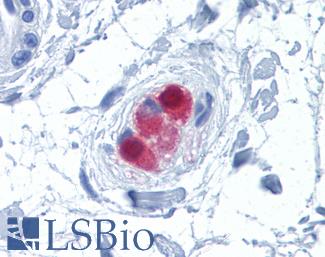

KRAS

Anti-KRAS antibody IHC of human placenta. Immunohistochemistry of formalin-fixed, paraffin-embedded tissue after heat-induced antigen retrieval. Antibody LS-B4683 concentration 5 ug/ml. This image was taken for the unconjugated form of this product. Other forms have not been tested.